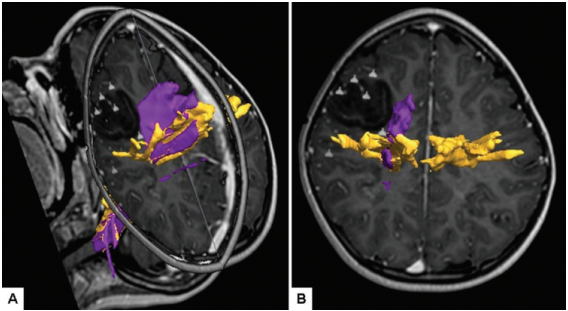

图示:斜位(A)和轴位(B) DT图像来自一名10岁女孩,她患有复杂的部分癫痫和右侧运动前胚胎发育不良神经上皮肿瘤(DNET)。病变深部与同侧皮质脊髓束的邻近性(黄色表示)和皮质脊髓/皮质脑桥的纤维的邻近性(紫色表示)很容易被识别。病变通过神经导航、术中超声和连续5次运动定位的前路手术切除。病人接受了全切除手术,术后恢复正常。